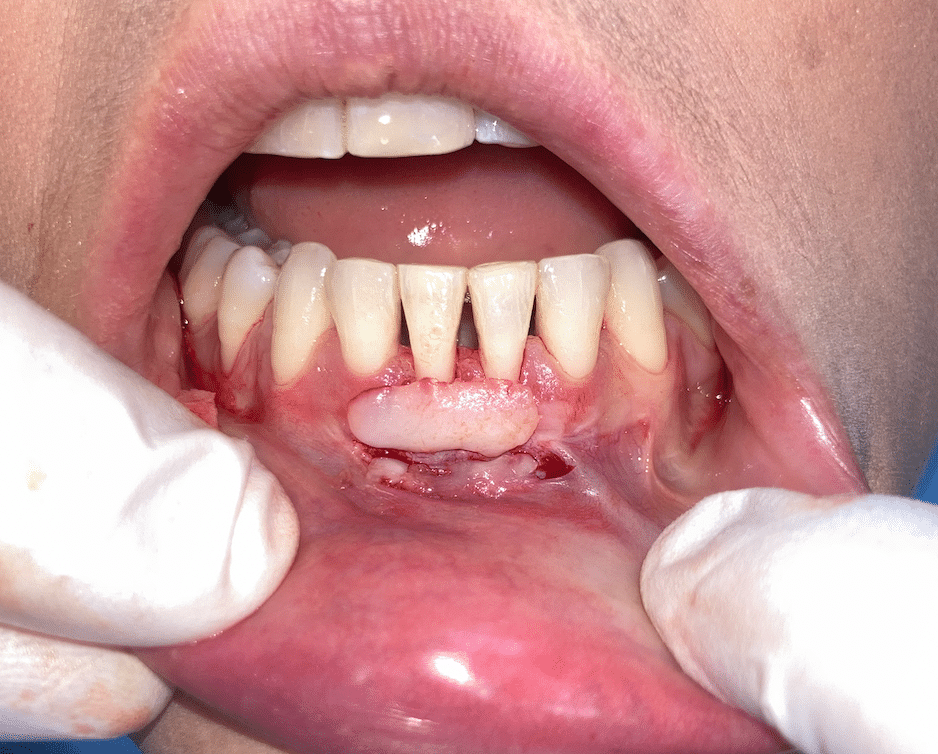

Dientes con recesión gingival, ¿cómo se ven?

Cuando hay recesión gingival, la encía se va subiendo (en los dientes superiores) o bajando en los dientes inferiores y deja expuesta una parte de la raíz del diente. En este sentido, el diente parece “crecer”, pero en realidad es la encía la que se ha retirado. A simple vista nuestros pacientes notan lo siguiente:

- Dientes más largos de lo normal.

- Pequeños espacios entre los dientes que antes no se apreciaban.

- Color diferente en la parte expuesta, ya que la raíz suele ser más amarilla que el esmalte.